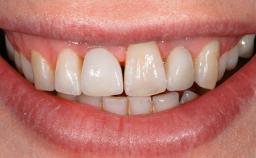

A 73-year-old woman was referred to the Division of Periodontology (University of Geneva School of Dental Medicine) after repeated unsuccessful treatment of a peri-implant infection. She was systemically healthy and did not smoke. The patient’s history revealed that, three years earlier, an immediate implant (Straumann Tapered Effect RN 4.8/4.1; Institut Straumann AG, Basel, Switzerland) had been inserted to replace the upper right central incisor. A metal-ceramic crown had been delivered using an adhesive resin cement. One year later, the patient had consulted another dentist due to discomfort in the soft tissues in the implant region. There was a suppurating peri-implant pocket, 10 mm deep. Peri-implant bone loss and excess luting cement were seen on the radiograph. The situation was treated with non-surgical debridement, amoxicillin, and repeated submucosal irrigation with a chlorhexidine digluconate solution. The patient was referred after the suppuration had persisted for several months.

Lip Line No exposure of papillae Exposure of papillae Full exposure of mucosa margin

Periodontal Phenotype Low-scalloped, thick Medium-scalloped, medium-thick High-scalloped, thin

Shape of Tooth Crowns Rectangular Triangular